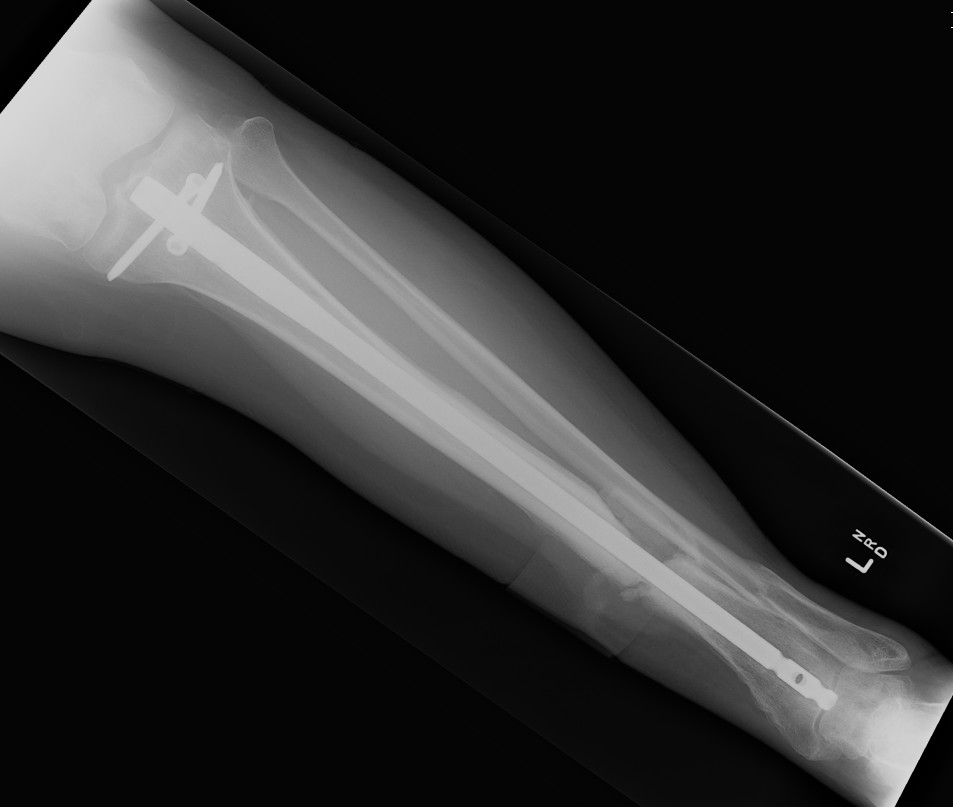

Tibial Nail 1Tibial Nail 2

Segmental shaft fractures

Segmental tibia 1Segmental tibia 2

Corey et al J Orthop Trauma 2018

- 95 treated with IMN

- nonunion rate 10%

https://pubmed.ncbi.nlm.nih.gov/29432320/